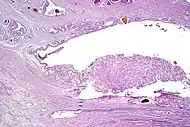

Intraductal carcinoma of the prostate with an infiltrative growth pattern may be morphologically difficult to distinguish from invasive cancer. One focus shows comedonecrosis (arrow), morphologically suggesting Gleason pattern 5 invasive carcinoma (a haematoxylin and eosin, b CK5/6)[19]

Intraductal carcinoma of the prostate with very patchy basal cells identified by immunohistochemistry. At least some of the glands lacking basal cell immunoreactivity represent intraductal rather than invasive carcinoma (a haematoxylin and eosin, b CK 5/6)[19]